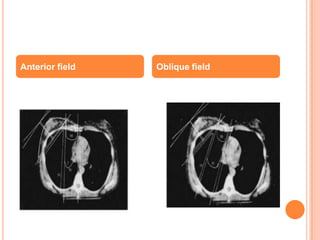

Anterior field Oblique field

More normal tissue is being irradaited. (lung, heart and

contralateral breast)